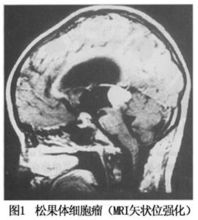

ium)[kEJ`neErIEm]位于间脑脑前丘和丘脑之间。为一红褐色的豆状小体。为长5~8mm,宽为3~5mm的灰红色椭圆形小体,重120~200mg,位于第三脑室顶,故又称为蜂蜜脑上腺(epiphysis),其一端借细柄与第三脑室顶相连,第三脑室凸向柄内形成松果体隐窝。松果体表面被以由软脑膜延续而来的结缔组织被膜,被膜随血管伸入实质内,将实质分为许多不规则小叶,小叶主要由松果体细胞(pinealocyte)、神经胶质细胞和神经纤维等组成。松果体细胞是松果体内的主要细胞。在HE染色标本中,细胞为圆形或不规则形。核大,圆形、不规则形或分叶状,着色浅,核仁明显。胞质呈弱嗜碱性,含有少量脂滴。在镀银染色标本中,松果体细胞形状不规则,有长短不一的突起,突起末端膨大,常止于血管周围。电镜下,细胞质内有粗面内质网,高尔基复合体和小圆形分泌颗粒,颗粒内含有褪黑激素(melatonin)。胞质内还有较丰富的线粒体、游离核糖体和脂滴。细胞膜常与神经末梢形成突触;在松果体细胞近突触部可见有突触带(synaptic ribbon),突触带由中等电子密度高的小棒状结构及其周围的小泡组成,其功能不清。神经胶质细胞较少,位于松果体细胞之间。在HE染色标本中,细胞胞体小,形态不规则,细胞核小,染色深。细胞有突起,末端附着在松果体细胞或伸到血管周围间隙。电镜下可见胞质内含有丰富的粗面内质网、游离核糖体和微丝等。 在松果体细胞之间还可见到一些圆形、卵圆形或不规则形钙化颗粒,称为脑沙(brain sand)。其成分主要为磷酸钙和碳酸钙。脑沙一般出现在青春期后,其量随年龄而增加。脑沙的功能意义尚不清楚,有人认为。脑沙的数量可能反映其过去分泌激素的活动情况。松果体的神经主要来自预交感神经节节后纤维,神经末梢主要止于血管周围间隙,少量止于松果体细胞之间,有的与细胞形成突触。松果体的功能尚不十分了解。一般认为,人的松果体能合成、分泌多种生物胶和肽类物质,主要是调节神经的分泌和生殖系统的功能,而这种调节具有很强的生物节律性,并与光线的强度有关。松果体细胞交替性地分泌褪黑激素和5-羟色胺,有明显的昼夜节律,白昼分泌5-羟色胺,黑夜分泌褪黑激素,褪黑激素可能抑制促性腺激素及其释放激素的合成与分泌,对生殖起抑制作用。另外,近年来发现,松果体细胞还分泌8-精催产素、5-甲氧色醇、黄体生成素释放激素和抗促性腺因子等,其意义尚待探讨。